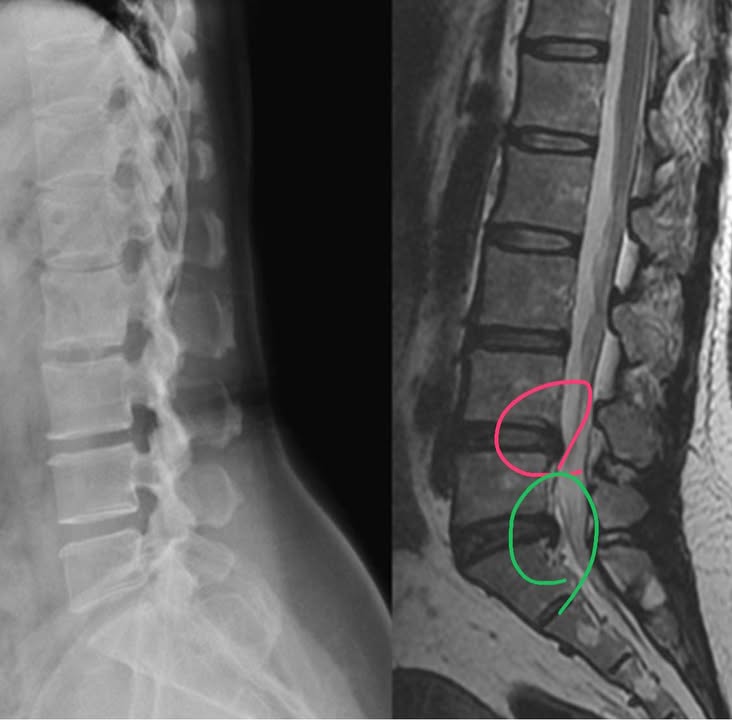

內湖胡小姐抱怨右邊腰痛連小腿快半年以上,當初坐在椅子上彎腰抱十公斤小狗突然閃到腰,原本以為一般閃休息就好,結果情況很快惡化,特別是麻很嚴重,右屁股到右小腿腳底內側然後右大拇指開始麻緊痠,到家中附近中醫針灸7-8次也接受傳統復健診所電療三個月,也到某診所打一次消炎止痛針,整天會麻,甚至走路超過十幾分就開始痛,疼痛指數大約到七分,由於狀況一直不佳才在2019年八月去內湖某醫學中心接受MRI核磁共振檢查,發現有兩節椎間盤突出,骨科醫師建議開刀,患者心生畏懼居然馬上跑走XDD(其實骨科醫師是為了她好),友人介紹來門診評估接受脊椎整合中醫微創療法

診斷:L4/L5;L5/S1 椎間盤突出